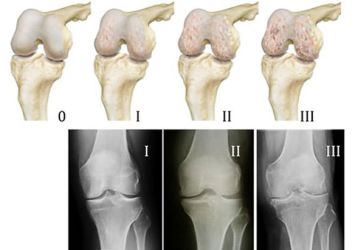

• Гонартроз — артроз коленного сустава. Чаще всего он встречается после 45 лет, хотя в последнее время заболевание «молодеет».